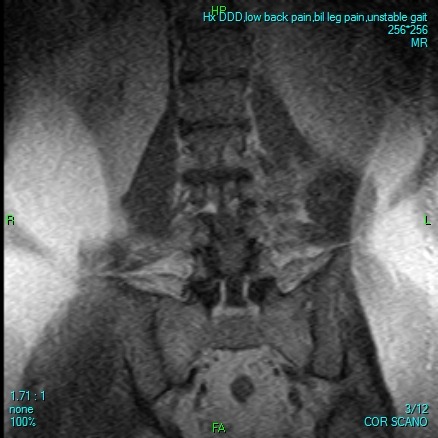

Some days he can barely stand or walk a few steps without collapsing in agony. Many nights, he lies alone, tears streaming down his face, praying for relief. His doctors have been clear: without urgent spinal surgery, he faces the devastating reality of becoming completely bedridden—possibly forever.

Desperate for relief, he trusted a foreign clinic that promised affordable treatment. Instead, they took advantage of him, leaving him stranded far from home in Mexico with no money to return. After months of struggle, honest and ethical doctors here in North America confirm they are prepared and able to perform the surgery he urgently needs. But the hospital requires $17,600 upfront to cover his Medicare deductible and uncovered costs before they can even admit him.